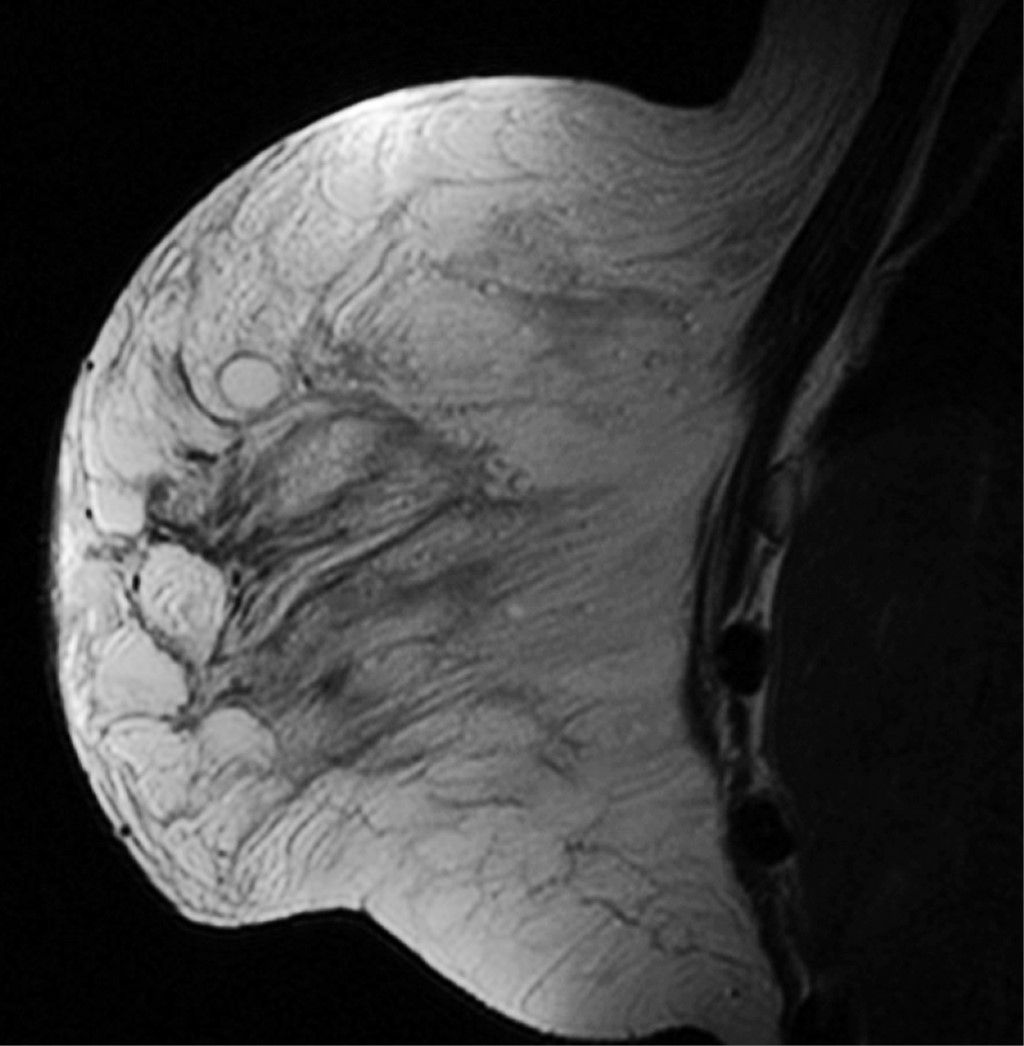

Resonancia magnética de mama con reporte de aumento de la densidad por la presencia de múltiples nódulos hiperdensos (Figura 2).

La enfermedad mamaria relacionada con la infiltración de materiales modelantes continúa siendo un problema grave de salud en nuestro país. La necesidad de una evaluación y clasificación adecuada en cada caso, tratamiento médico oportuno y tratamiento quirúrgico acorde con las condiciones de cada paciente aceleran el proceso de detección, manejo sintomático y definitivo. La resonancia magnética nuclear ha demostrado ser el único estudio útil para determinar el grado de afección por el material modelante. Es de gran importancia el manejo multidisciplinario, para evitar el abandono del tratamiento por parte del paciente.

Figura 2